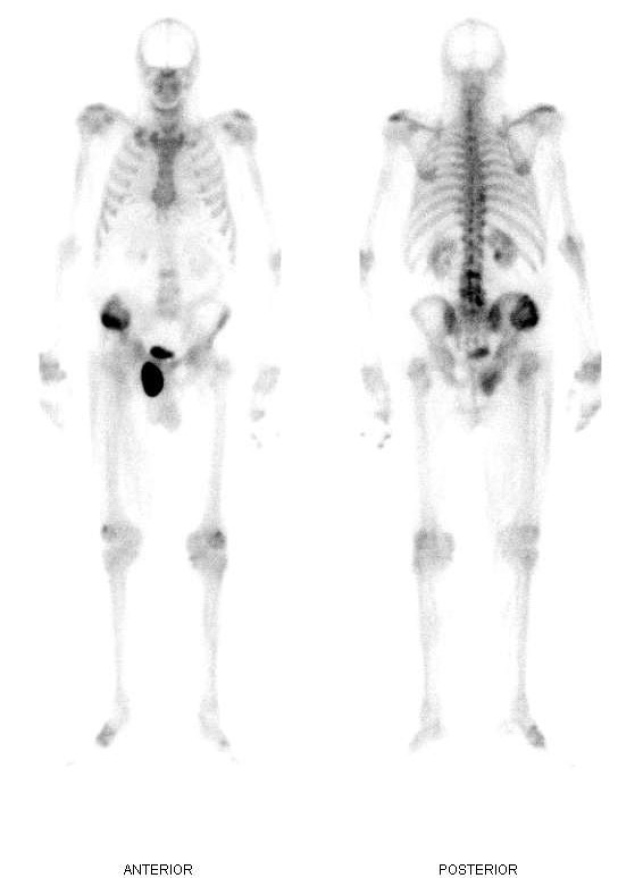

Se presenta el caso de un paciente masculino de 70 años con un único antecedente de carcinoma basocelular invasivo previamente operado, al cual le es solicitado un centellograma óseo debido a una lesión en alerón ilíaco derecho reportada en una tomografía computarizada (TC) de pelvis. Se realiza rastreo de cuerpo completo con 99mTc-MDP, imágenes estáticas de pelvis y SPECT. En el estudio de cuerpo completo se observó lesión en cresta ilíaca derecha, hipercaptante con componente lítico central, junto con un foco de hipercaptación de intensidad similar a la vejiga, proyectado por debajo de la rama superior del pubis derecho, de aspecto sacular (fig. 1). En las imágenes segmentarias con vistas anteroposteriores y laterales se evidencia que el hallazgo es de ubicación anterior respecto a la rama isquiopubiana derecha (fig. 2). En el estudio SPECT se confirma una gran lesión hipermetabólica con área central fotopénica de aspecto redondeado, que protruye de la cresta iliaca derecha y no respeta bordes anatómicos. Además, se evidencia claramente la existencia de conexión entre la vejiga y la zona hipercaptante de aspecto sacular ya mencionada (figs. 3 y 4).